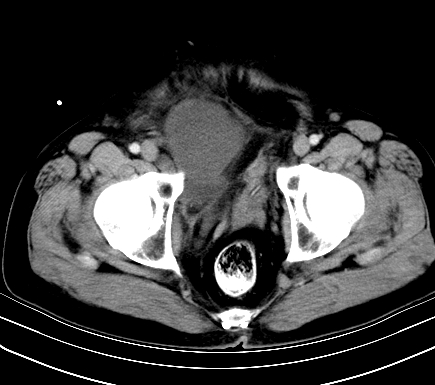

标题: CT19729B:男,74岁,因腿疼就诊,查体触腹部肿物, [打印本页]

标题: CT19729B:男,74岁,因腿疼就诊,查体触腹部肿物,

增强扫描

动脉期

【临床症状】

分析:

1、老年男性,易患恶性肿瘤;

2、腿痛就诊,一部分恶性肿瘤的患者会分泌一种激素,使凝血机能发生障碍,促下肢静脉血栓形成,致腿痛,有时往往为首发症状。因此,肿瘤不除外恶性肿瘤。

【ct表现】

1、肿块巨大,往往位于腹膜后,长大后才引起症状而就诊;那么位于腹膜后的肿瘤80%为恶性肿瘤。

2、实性肿瘤,增强扫描轻度不均强化,实性肿瘤一般不是好东西。

3、肿瘤边缘似见少许脂肪样密度。

4、腹膜后未见肿大淋巴结,但肿瘤于临近的肠管及组织接触紧密。

【诊断】

腹部占位,考虑位于腹膜后的恶性肿瘤,脂肪肉瘤(实体型)可能性大。

【分析】

1、腹膜后的肿瘤少见,但种类繁多,包括脂肪肉瘤、纤维组织细胞肉瘤、纤维肉瘤、平滑肌肉瘤、恶性畸胎瘤、神经肉瘤、神经母细胞瘤、血管肉瘤及横纹肌肉瘤等,其中脂肪肉瘤为较常见的一种肿瘤。

2、增强扫描强化不明显,除脂肪肉瘤以外,一般肿瘤强化中度以上。脂肪肉瘤可不强化或轻度强化。

术后病理结果:腹膜后脂肪肉瘤。